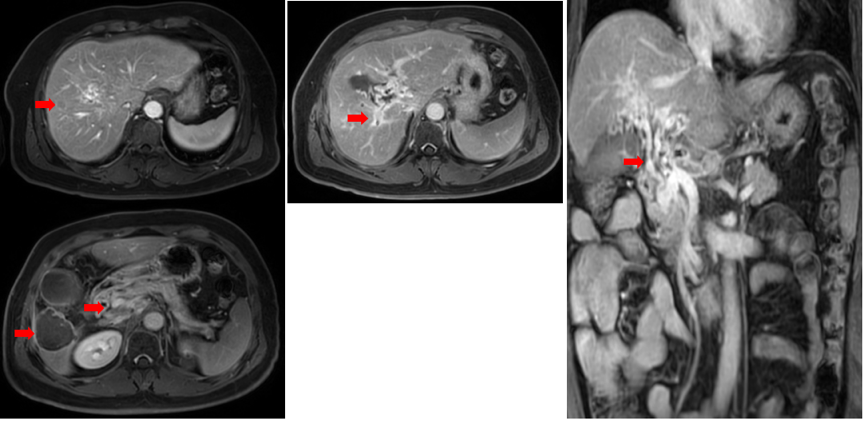

2021年1月18日复查上腹部MRI示,肝内病灶无明显活性,门脉右支癌栓部分消退,腹膜后淋巴结仍为稳定状态,总体评价PR(图5)。

图片

图5.2021年1月18日复查上腹部MRI